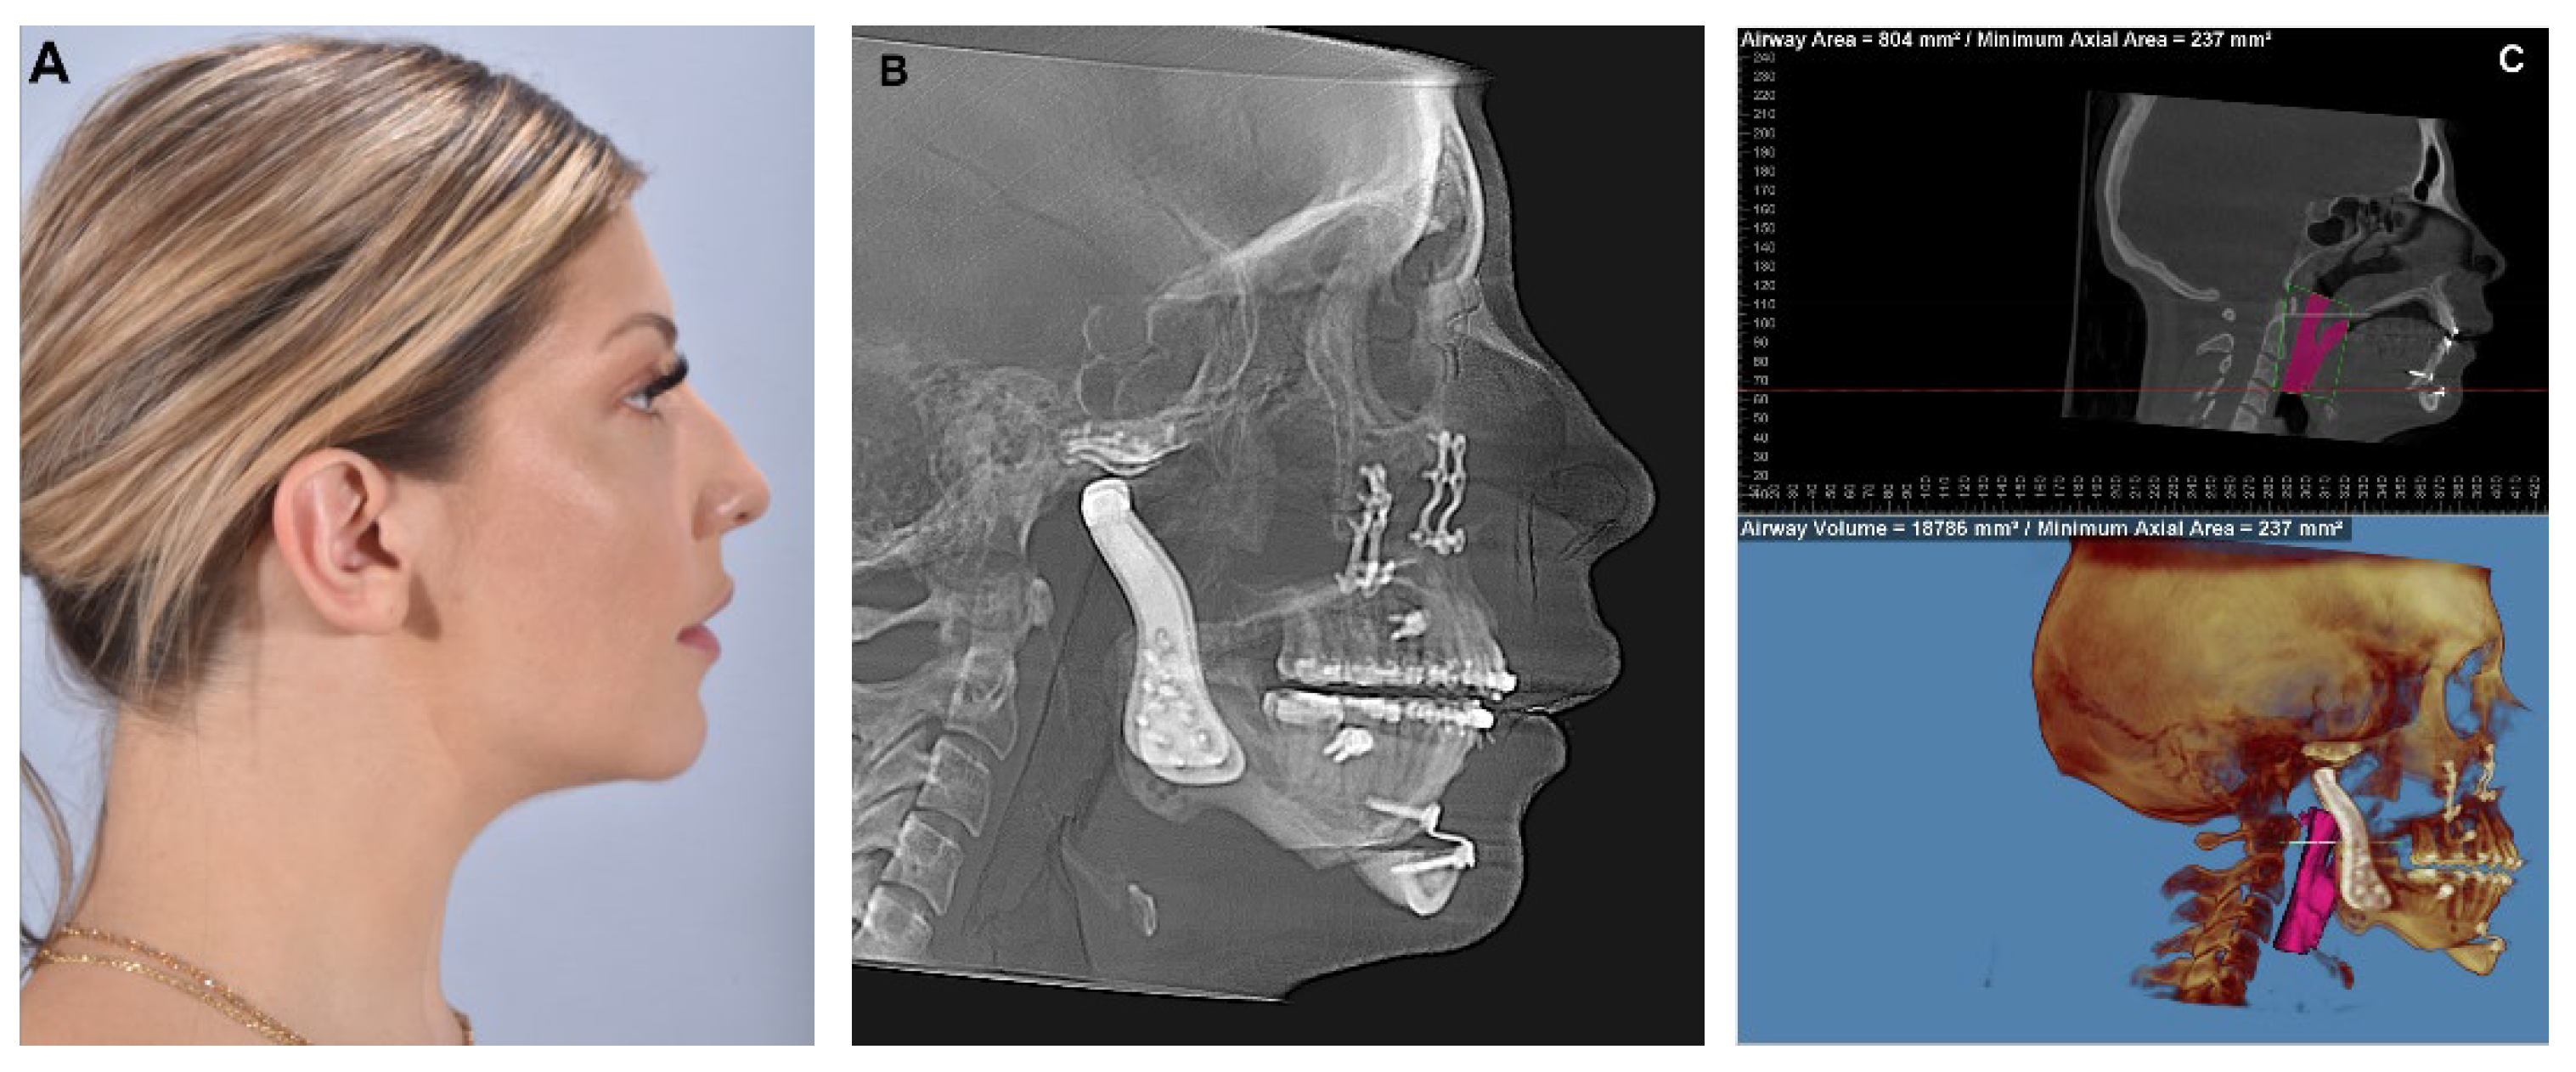

When assessing a patient who requires TMJ reconstruction, it is crucial to consider that approximately two-thirds of these patients can experience significant advantages by undergoing concurrent orthognathic surgery [11]. This decision is made following a comprehensive clinical examination, which includes a thorough assessment of the patient’s complaints, expectations and clinical exam including dental models or intraoral dental scans, as well as the utilization of radiographic aids (panoramic Xray, lateral cephalogram and cone-beam computed tomography (CBCT) or computerized tomography (CT) scan) to gather additional information. End-stage TMJ pathology, particularly when condylar degeneration is present, can lead to loss of posterior vertical height and high occlusal plane angles, Class II malocclusions, anterior open bite and decreased airway space (Figure 1).

Figure 1. (A) 24-year-old female with bilateral condylar resorption, high occlusal and mandibular plane angles, retruded mandible, severe Class II appearance and anterior open bite. (B) Lateral cephalogram confirming clinical findings. (C) TMJ views from CBCT confirm severe condylar resorption. (D) Airway analysis shows severely decreased airway space (Airway volume = 10,923 mm3, Minimum Axial Area = 120 mm2).